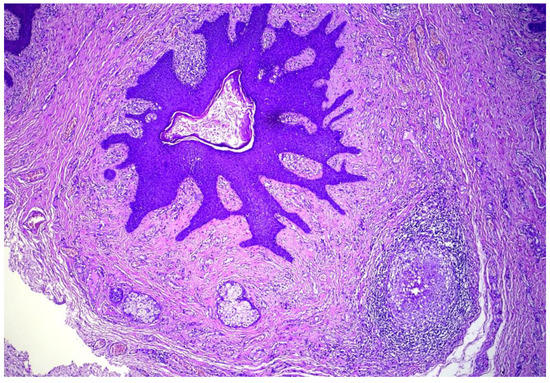

Genital Folliculosebaceous Cystic Hamartoma: A Case Report and Concise Review of the Literature

2. Detailed Case Description